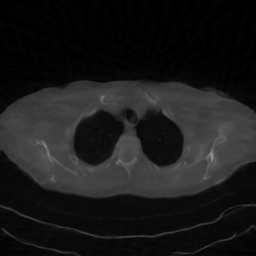

Finally, we perform a brief ablation study, the results of which are shown in Figure 5. Here, we consider one test image reconstructed from nα=30,45,60n_{\alpha}=30,45,60 angles, respectively, and display the results obtained by separately applying the two proposed techniques, namely FBP-based initialization and step-size scheduling in the inversion algorithm. We immediately notice that without the proposed initialization, the reconstructed image obtained by the generative model represents a totally different patient's slice, showing the importance of a correct initialization for such an ill-posed and non-convex optimization problem. The step-size scheduling, on the other hand, is important for reducing noise and enhancing contrast, both in fine details and in low-contrast regions, but it does not largely affect metrics and is definitely less impactful than the initialization. Finally, we note that the bottom-right image was obtained using the DMPlug algorithm, which differs from the proposed method in these two modifications, as well as by the inclusion of a regularization function applied to 𝒢(𝒛)\mathcal{G}(\bm{z}), as in (3). The study confirms the effectiveness of the proposed techniques incorporated in RD-DGP.

nα=30n_{\alpha}=30

FBP Init. Rand Init.

Cosine sched.

Refer to caption PSNR: 34.48 SSIM: 0.8802 Refer to caption PSNR: 19.59 SSIM: 0.4048

No sched.

Refer to caption PSNR: 34.22 SSIM: 0.8782 Refer to caption PSNR: 19.88 SSIM: 0.4772

nα=45n_{\alpha}=45

Refer to caption PSNR: 37.27 SSIM: 0.9299 Refer to caption PSNR: 19.08 SSIM: 0.4318

Refer to caption PSNR: 33.95 SSIM: 0.8694 Refer to caption PSNR: 19.80 SSIM: 0.4148

nα=60n_{\alpha}=60

Refer to caption PSNR: 37.18 SSIM: 0.9431 Refer to caption PSNR: 19.45 SSIM: 0.4003

Refer to caption PSNR: 32.79 SSIM: 0.8641 Refer to caption PSNR: 19.07 SSIM: 0.4541

Figure 5: Ablation study on sample C081-35 under sparse-view CT. Each block reports reconstructions (with PSNR/SSIM overlaid) obtained with different combinations of FBP initialization (Yes/No) and step-size schedule (Yes/No). From left to right, the number of projection angles nαn_{\alpha} is 3030, 4545, and 6060.